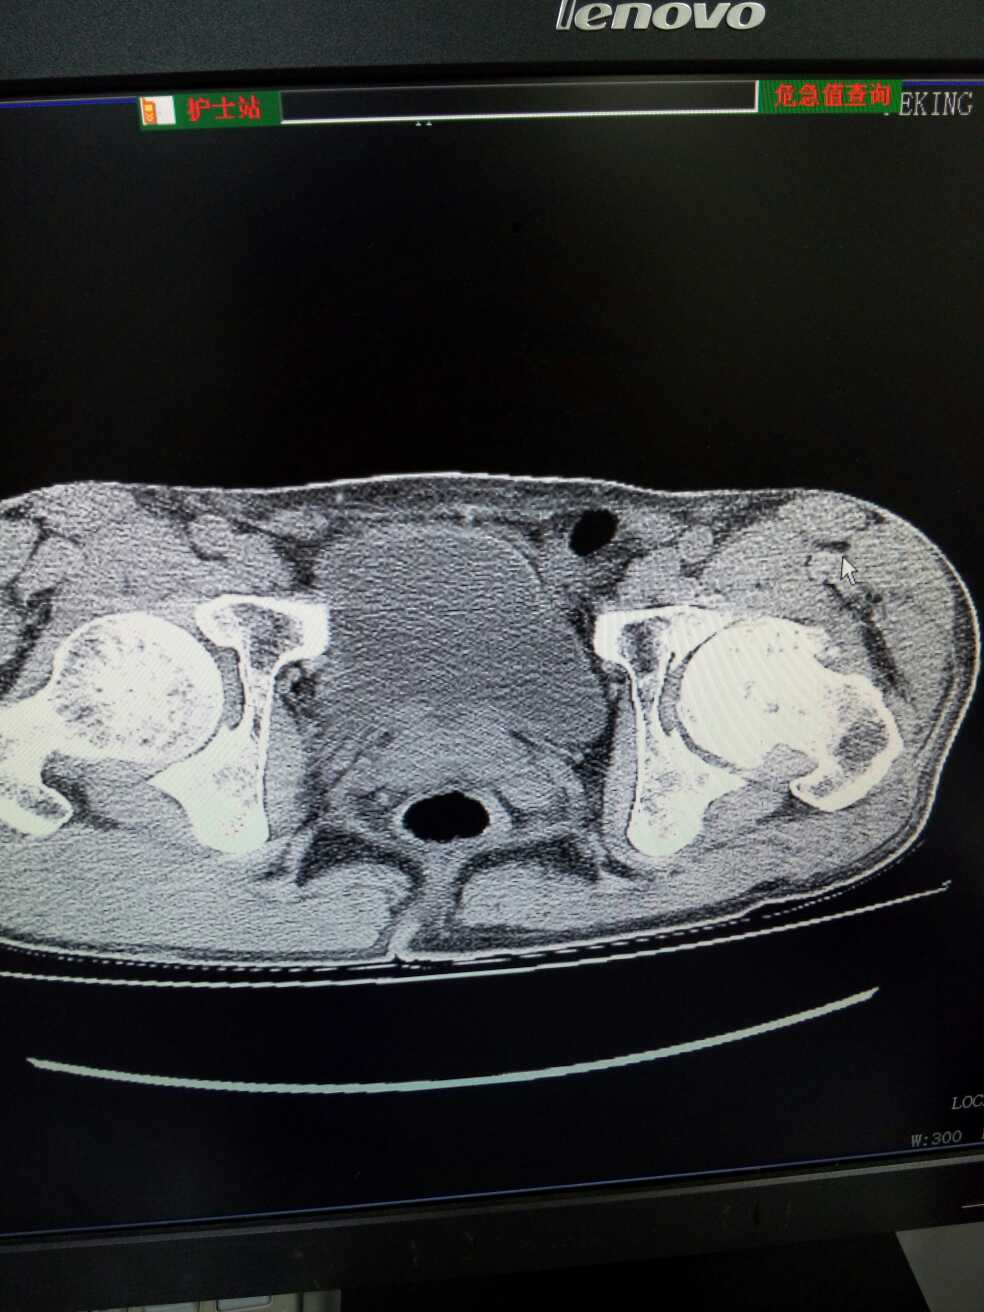

股骨骨折。髋关节置换手术后,髋关节末端脱落。

男,59岁,左髋关节活动受限4年余,加重1年。从片子上看能看出什么问题?